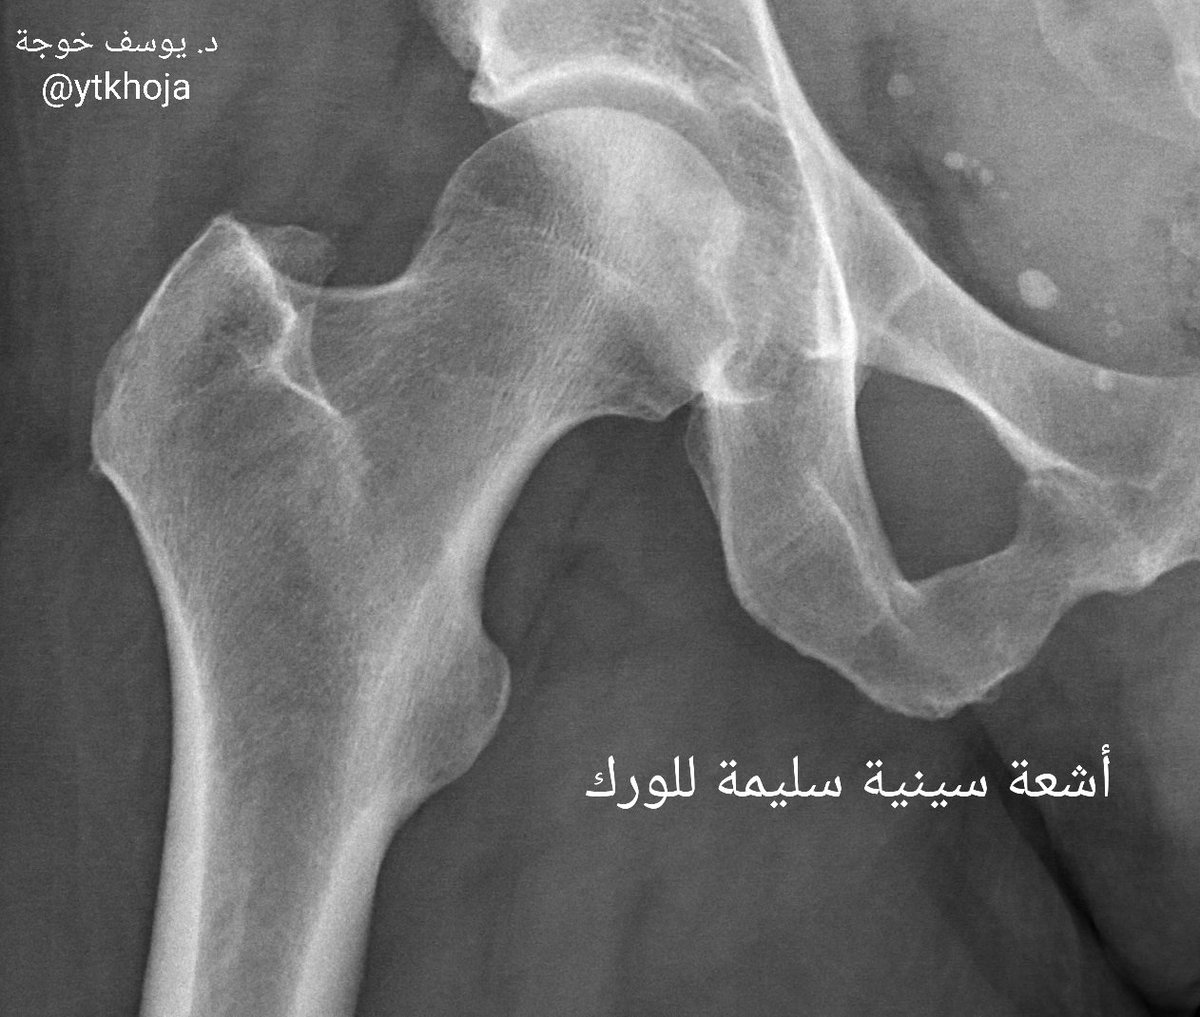

الأشعة السينية:

عادة لا تظهر شيئاً وتكون طبيعية ما عدا إذا كان السبب وجود أجسام غريبة متحركة داخل المفصل